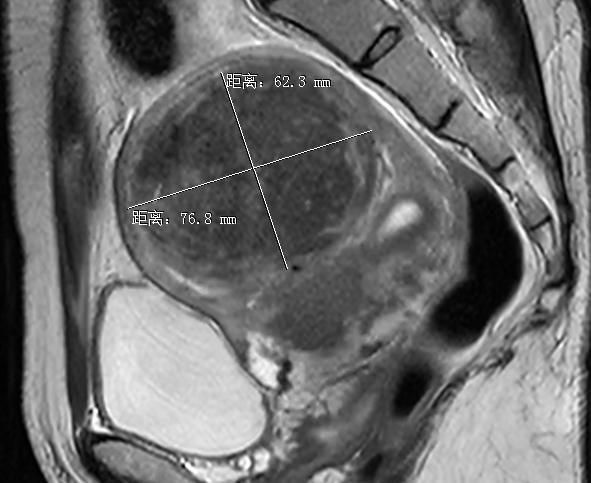

肌瘤开始还不大,就2cm,蚕豆大小,完全不用理会,可是每年的检查提示这个肌瘤实在是顽强,由2cm逐渐增大到了8cm,得有石榴这么大了,不但肌瘤在增大,还逐渐出现了月经量也开始增多,经期也更长了,小便次数也多了起来,夜尿增多让她是不胜其烦,到了该和这个肌瘤做一个了断的时候了。但是医生的建议:子宫切除,真是何女士无法接受的,失去孩子已经够痛苦,难道还要失去孩子的老房子吗?

盆腔MRI检查提示肌瘤明显